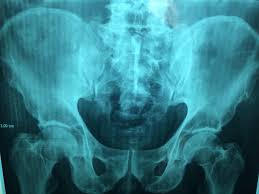

앉아 있을 때 느껴지는 불편감

고관절 통증은 걷거나 움직일 때뿐 아니라 가만히 앉아 있을 때도 나타날 수 있습니다.

• 오래 앉아 있으면 엉덩이 통증

• 의자에서 일어날 때 뻣뻣함

• 장시간 운전 후 통증

특히 장시간 앉아 있다가 처음 움직일 때 통증이 심해진다면 고관절 내부의 마찰이나 염증 가능성을 생각해볼 수 있습니다.